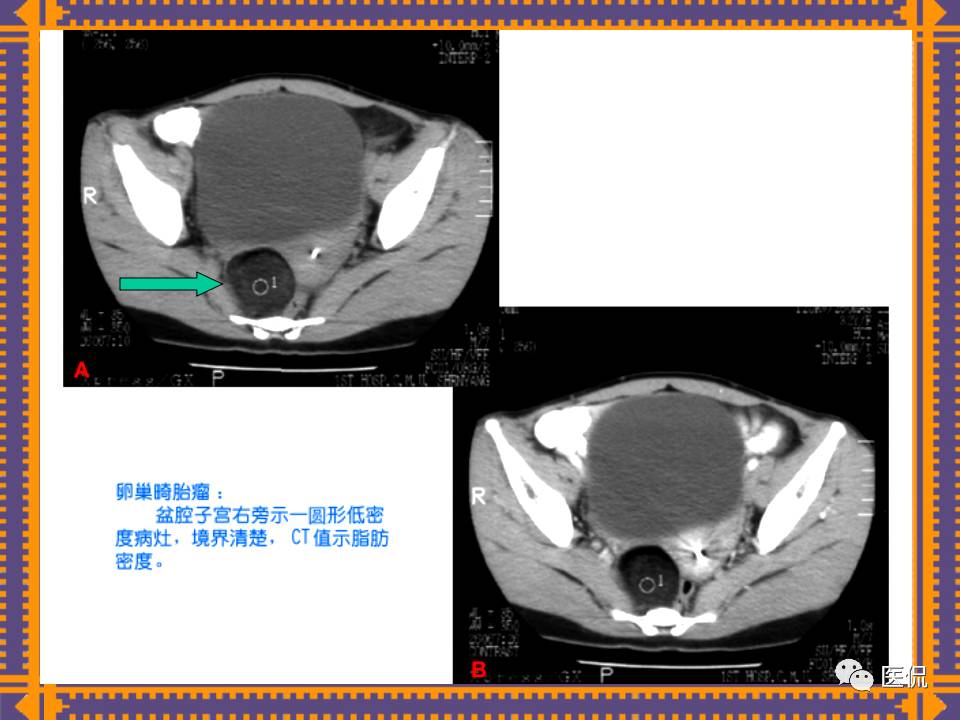

这篇PPT对男性生殖系统疾病:前列腺增生、前列腺癌;女性生殖系统疾病:子宫肌瘤、子宫癌、卵巢囊肿和卵巢肿瘤以及腹膜后间隙疾病进行了详细讲解。